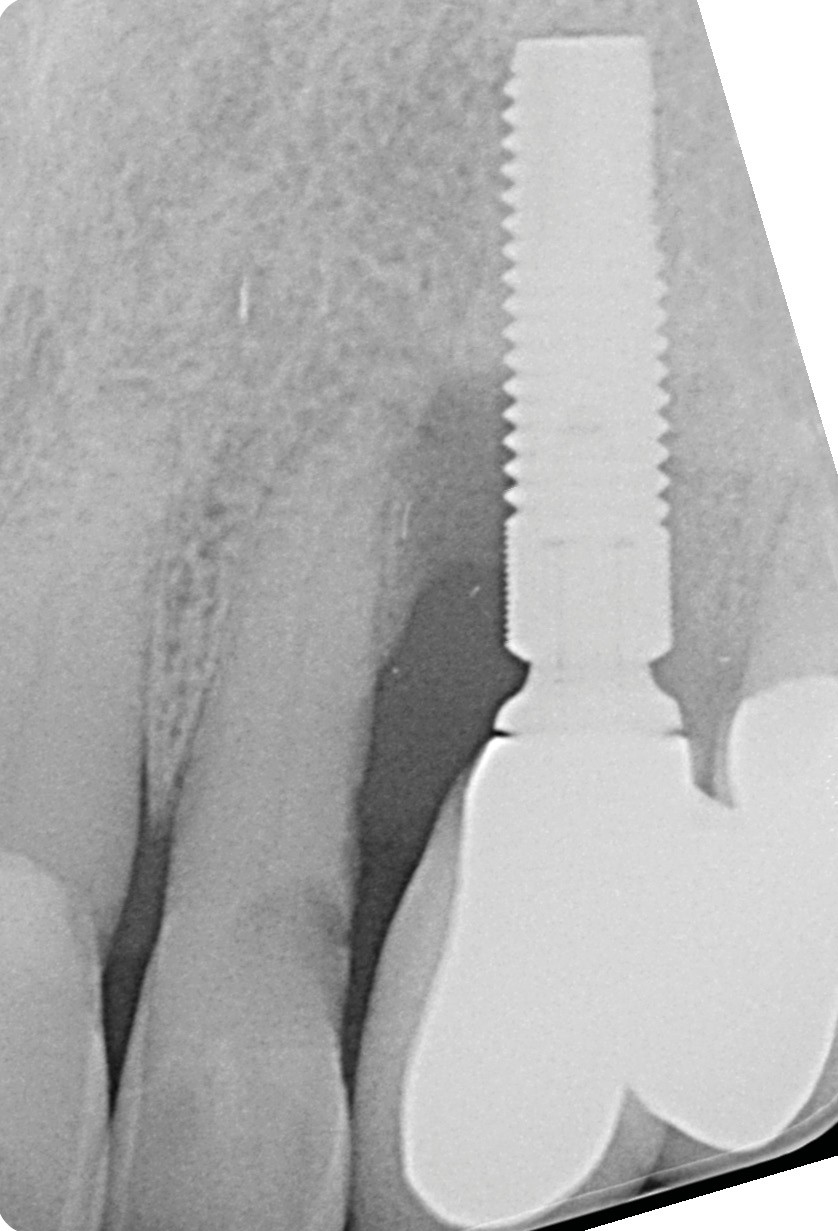

L’implant

- Site 23

- Mis en place il y a 12 ans